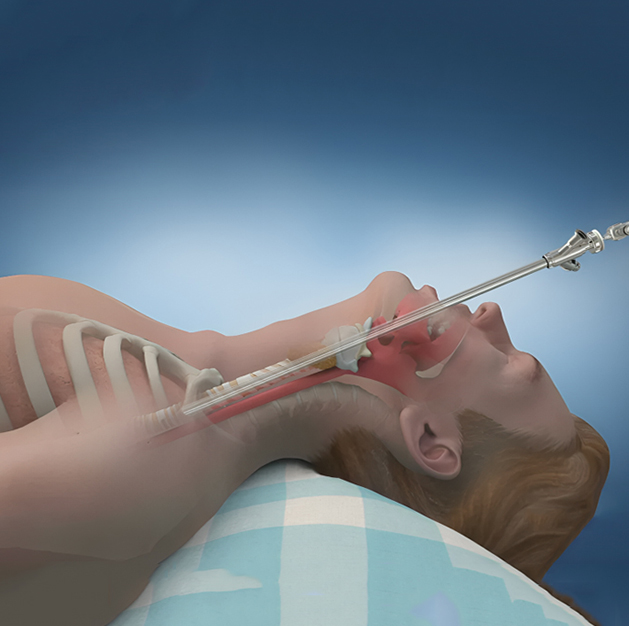

Fibreoptic Bronchoscopy